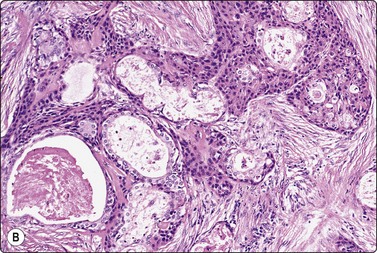

Basaloid squamous carcinoma (Fig. 4.7) is a rare distinct variant of squamous cell carcinoma of the head and neck, which is clinically aggressive and has a predilection for the hypopharynx and the tongue. The smear findings are of squamous cell carcinoma without specific features, but a predominance of basal cells may make the distinction from the solid variant of adenoid cystic carcinoma difficult.43

image

Fig. 4.7 Basaloid squamous cell carcinoma of head and neck

(A) Poorly differentiated cells with squamous features (MGG, HP; (B) Tissue section mimicking adenoid cystic carcinoma (H&E, IP).